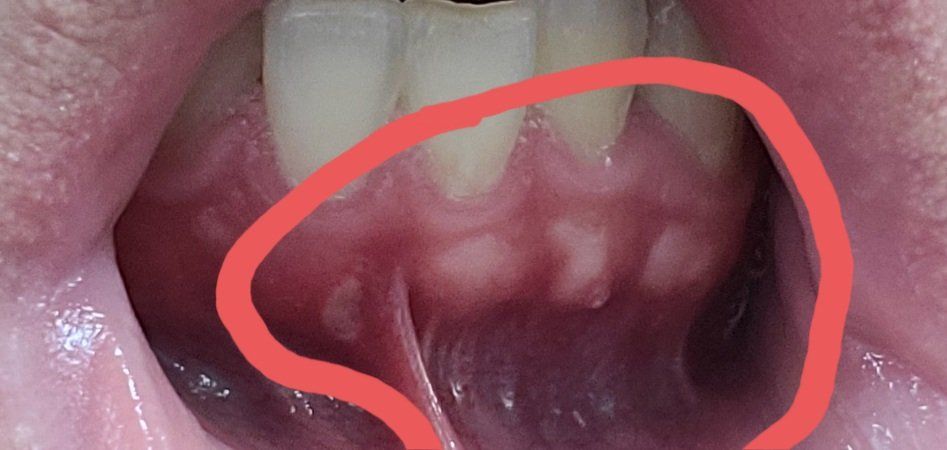

잇몸에 이렇게 흰색으로 올라왔는데 이게 뭔가요?

일주일정도 잇몸이 이렇게 하얗게 부어서 통증이 좀 있습니다.

몇일 지나면 사라질거라고 생각해서 내버려두었더니 시간이 지나고 흰색이 그대로인거 같습니다.

제가 리스테린을 사용하고서부터 이런거 같은데 리스테린때문은 아니겠죠?

• 1번 째 사진

잇몸뼈가 밖으로 자라나오게 된다면 잇몸이 햐얀색으로 보일수 있습니다.

외골증인데 문제가 되지는 않습니다. 잇몸이 얇기 때문에 딱딱한 음식을 먹거나 한다면 상처가 생기거나 할수 있어요.

치아 뿌리 부분에 있는 치조골 및 치아가 비춰보이는 것입니다. 즉 치아 머리 아래 부분이 보이는 것으로 치아 앞니는 잇몸이 얇아서 다른 부위에 비해 잘 보일 수 있으며 지금과 같이 잇몸 조직을 당기게 되면 훨씬 더 잘 보이게 됩니다.

현재 보이는 사진으로만 보면 특별한 염증은 아니고, 잇몸뼈가 튀어나온 부분이 잇몸이 얇아서 하얗게 보이는것으로 보입니다.

현재 통증이 없다면 큰 문제는 없을것으로 보입니다.

정확한것은 치과에서 검사를 받아보시기 바랍니다. 감사합니다.